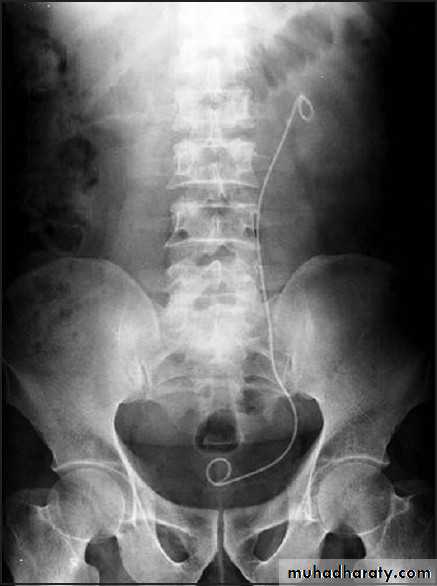

URETERAL STENTS

• Ureteral stents are a mainstay in the urological armamentarium.

• utilized in:

• treatment of urolithiasis including postureteroscopy

• preshockwave lithotripsy

• to relieve symptomatic renal colic

• to provide urinary drainage in nongenitourinary causes of ureteral obstruction, such as pregnancy and malignant ureteral obstruction

• To serve as a surgical landmark for ureteral identification in order to avoid iatrogenic ureteral injury in abdominal or pelvic surgery.

• Ureteral stents decrease the frequency and amplitude of ureteral contractions.• The ureter and ureteral orifice are theorized to passively dilate from the stent, thus facilitating drainage.

• Available in various sizes, designs & materials.